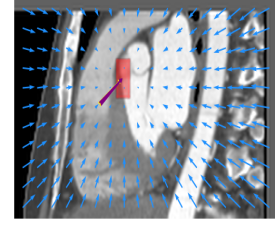

Finally, the proposed network was evaluated for the detection of five additional landmarks: the left coronary ostium, the bifurcation of the LM into the LAD and the LCx, and the origin of the left, non-coronary, and right aortic valve commissures (see Fig. 2). Fig 3 shows vector fields visualizing the predicted displacement vectors in three viewing planes in an image from the test set (for more results, see Appendix). Table 3 lists the Euclidean distance errors between the predicted landmark locations and the reference landmark locations. In addition, box-and-whiskers plots are shown in Fig 4. The best results were obtained for the origin of the right aortic valve commissure. Detection of the origin of the left aortic valve had the most narrow distribution. Outliers were seen during detection of the right ostium, the bifurcation of the LM, and the origin of the non-coronary, and the left aortic valve commissure.

Refer to caption Refer to caption Refer to caption

Figure 3: Vector fields visualizing the predicted displacement vectors in the axial, coronal, and sagittal plane in an image from the test set where detection of the right coronary ostium was performed. The magnitudes of the vectors should point at the right ostium, but they are rescaled for visualization purposes. The red squares indicate posterior probabilities larger than 0.5, obtained by the classification network for image patches. Reference and computed landmark annotations are indicated with a yellow and purple arrow, respectively.